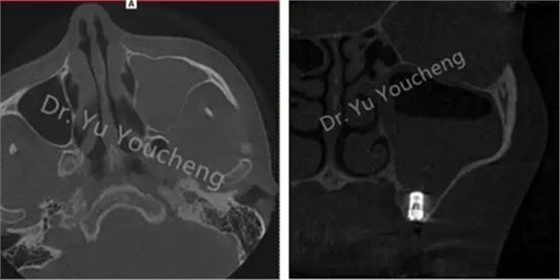

系列課開(kāi)播前小編為大家預(yù)告了一例上頜竇外提升術(shù)后種植體方向改變的病例,當(dāng)時(shí)頓生種種疑惑:“真的么?怎么會(huì)?怎么辦!!”在本次課程中余教授給出了答案:上頜竇外提升同期種植有一重要的因素,即種植體初期穩(wěn)定性的獲得。該患者由于其骨量的嚴(yán)重不足,雖然可通過(guò)大直徑覆蓋螺絲保證種植體不至于滑落,但隨著竇粘膜的運(yùn)動(dòng)和部分移植骨的吸收,種植體方向最終受到了影響,這也提示我們?cè)谥贫ㄖ委熡?jì)劃過(guò)程中應(yīng)慎重考慮這一因素,以確保更好的種植預(yù)后效果。